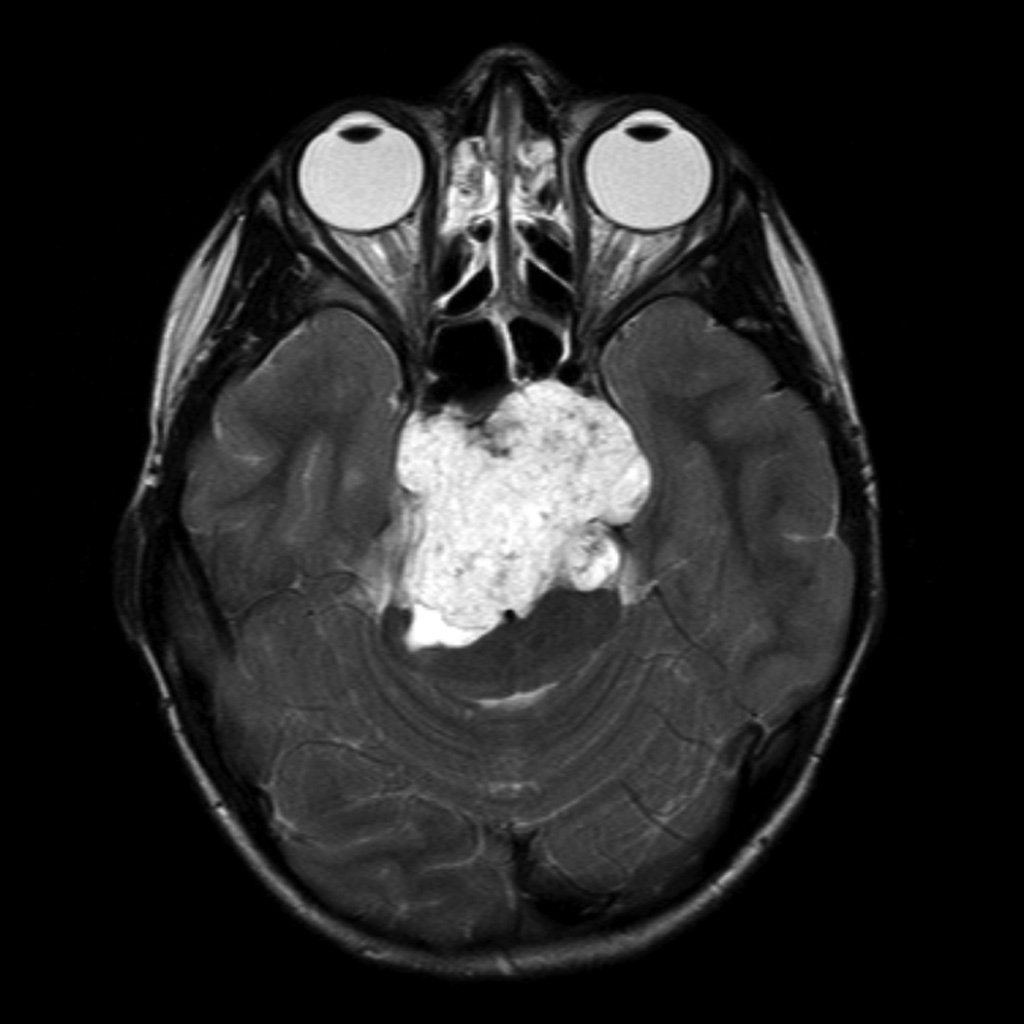

对于脑脊索瘤显微外科手术,国际颅底肿瘤手术教授巴特朗菲教授是擅长的,巴特朗菲教授在术中核磁、神经导航等高复杂设备的辅助下,其脑脊索瘤平均切除率达到了90%以上。在国内,一位95后小姑娘雯雯(化名)身患桥前斜坡脊索瘤,斜坡位置的脊索瘤手术难度较大,难以切除干净,较易复发。雯雯在国内一次手术后仍然还有很大一部分残留,效果不理想,而国内医生告知二次手术风险太大,建议保守治疗。后经过INC的联系,找到了巴特朗菲教授,巴特朗菲教授为雯雯实施了从枕下乙状窦后入路对脑干实施广泛解压切除术,手术很成功,手术切除率达到了95%以上。

雯雯脊索瘤影像图